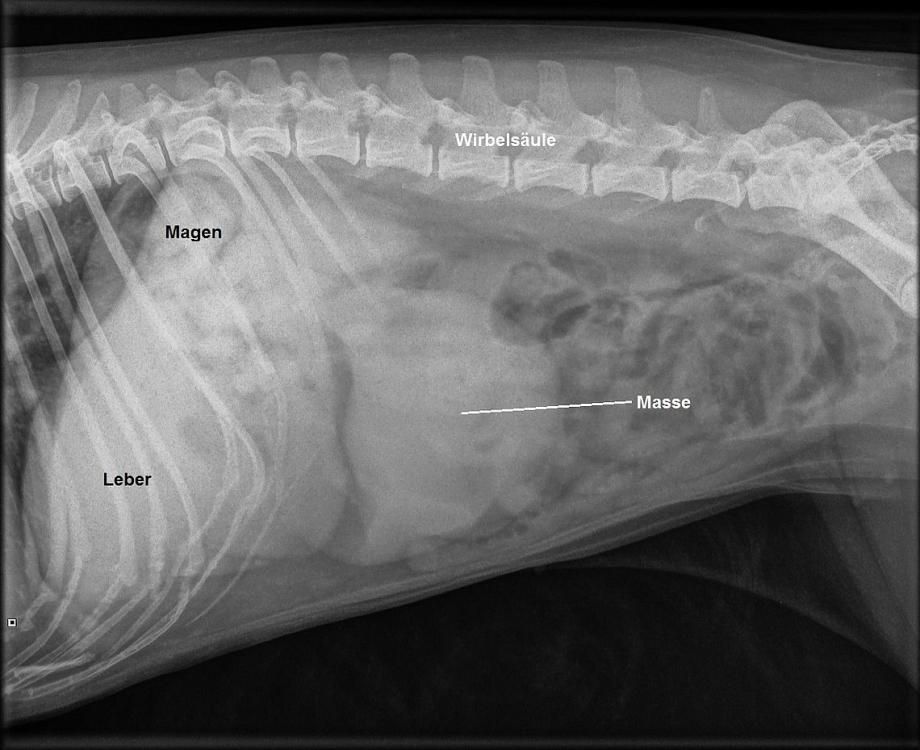

Eine Blutuntersuchung verläuft unauffällig, ebenfalls verläuft die Suche nach Veränderungen von Herz und Lunge mittels Röntgenaufnahmen des Brustkorbes ergebnislos. Bei einer Röntgenaufnahme des Bauches wird aber ein Knoten entdeckt, und Oryad wird uns zur weiteren Abklärung des Problems zur Ultraschalluntersuchung überwiesen.

Obwohl nun bekannt ist, dass sich im Bauch des Hundes ein Knoten verbirgt und dieser zielgerichtet abgetastet werden kann, erweist sich die Masse als nicht ertastbar. Im Ultraschall findet sich dann aber ein knapp 5 cm messender, kugeliger Knoten innerhalb der Milz. Der Knoten zeigt eine heterogene (uneinheitliche) Echotextur und enthält auch kleine Hohlräume, welche mit Flüssigkeit gefüllt scheinen. In der Bauchhöhle findet sich aber keine Flüssigkeit, die restlichen Bauchorgane erscheinen unauffällig, und auch ein kurzer Ultraschall des Herzens verläuft unauffällig.